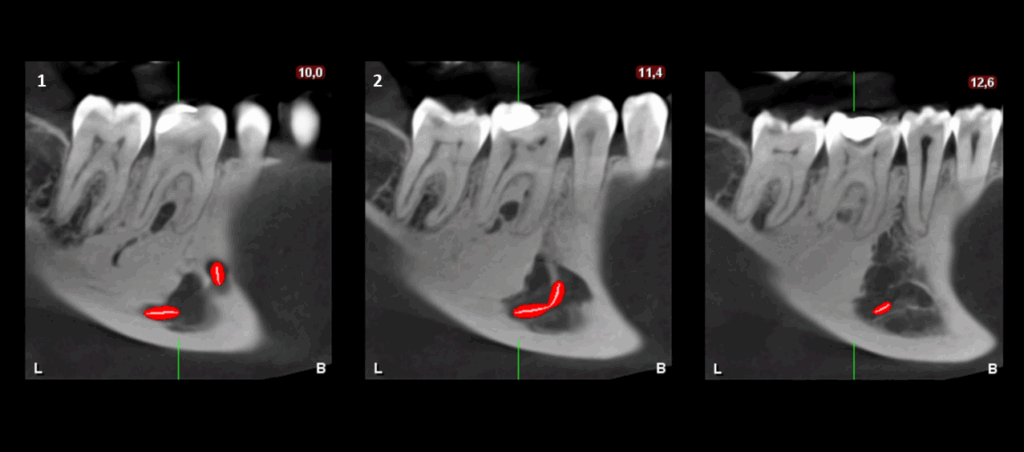

En el estudio complementario mediante tomografía computarizada de haz cónico (TCHC), se observa la obturación subextendida de conductos en la raíz mesial de la pieza 37, se confirma el proceso osteolítico periapical y el aumento de la densidad ósea circundante con extensión hacia el conducto dentario inferior. En la pieza 46 se observa una restauración oclusal hiperdensa con material restaurador isodenso subyacente próximo a cámara pulpar y se corrobora el aumento de la densidad ósea periapical que además se extiende hacia la tabla ósea lingual.

CORTES TRANSAXIALES